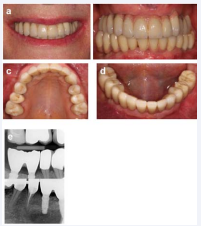

Three weeks later we cemented the final work and took X-rays (Figure 10 a-e).

Figure 10: Finally finished after nearly one year after the initial consultation (a) en-face smiling, (b) en-face with retracted lips, (c) upper jaw and (d) lower jaw. (e) Bite-wing of the right side and peri-apical X-ray of the lower left side one year after completion of the restoration, a root canal treatment had to be performed on tooth 34 due to a peri-apical inflammation.

As can be seen in Figure (10b) the posteriors were restored in cross bite. Main reason was the palatal oriented adsorption of the upper jaw and the buccal oriented adsorption of the lower jaw. This is a regular occurrence for patients with long established edentulism. From start to finish we needed a total of 12 months. The patient’s teeth are monitored and cleaned half yearly.